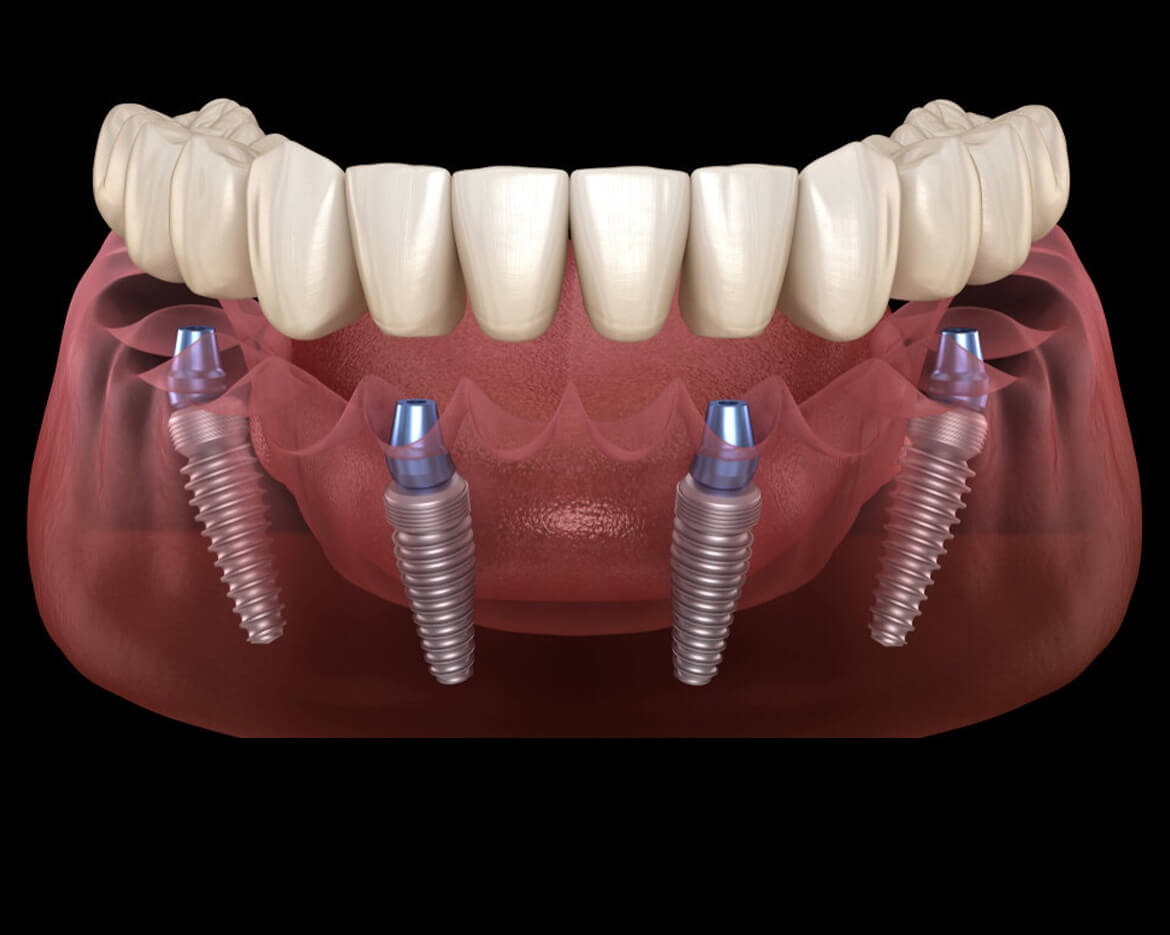

Implantologia E Chirurgia

L'implantologia dentale è la specialità medica che si occupa dell'inserimento